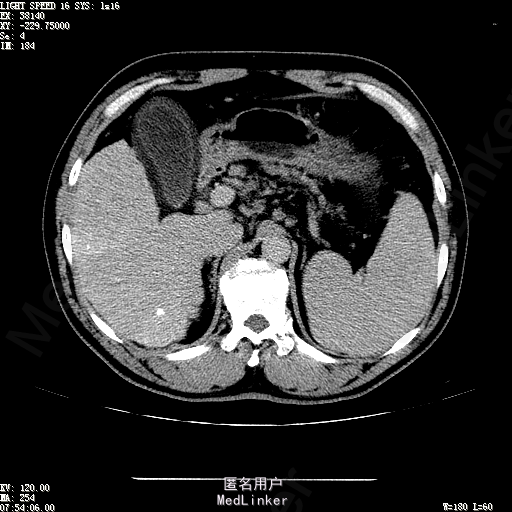

主诉:肝癌TACE治疗后36天 病史:患者两年前体检发现丙型肝炎病毒标志物阳性,于当地医院就诊诊断为"丙肝肝硬化",口服药物治疗,具体用药不详。定期复查肝功及肝脏影像学检查,2月前于医大二院行肝脏增强磁共振检查发现肝S6段动脉期增强结节,36天前在我院行DSA肝动脉造影明确"原发性肝癌"诊断并行"TACE"治疗,术后恢复良好,现患者为进一步行肝癌局部消融治疗来诊。

诊断:1、丙肝肝硬化 代偿期;2、原发性肝癌 S5段、S6段 该患诊断明确,既往曾行TACE治疗肝癌,S5段、S6段近右肾上极2处碘油沉积明确,S5段者较大,约2.31cm。超声显示清晰,为防止癌灶复发,适合行射频消融治疗。